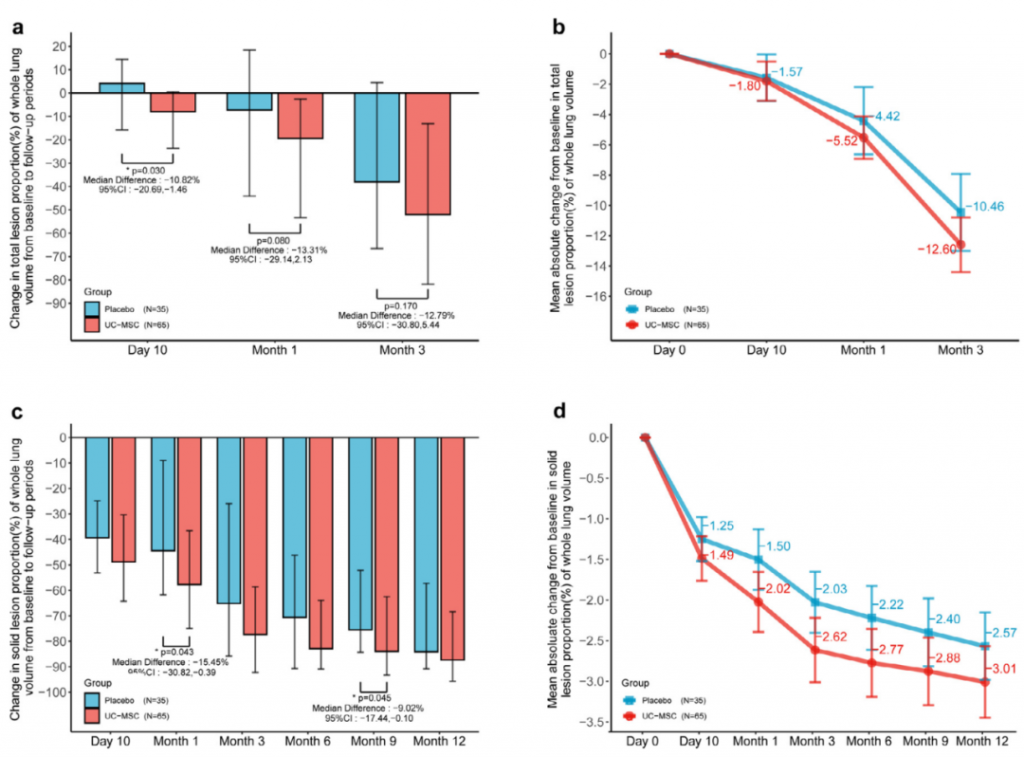

與安慰劑組相比,人臍帶間充質干細胞修復組全肺病變體積改善了10.8%,并且人臍帶間充質干細胞修復組在每一個隨訪節點都顯示出固體組分病變體積比例減少。此外,人臍帶間充質干細胞組有17.9%的患者在12個月時CT圖像變為正常,而安慰劑組沒有。